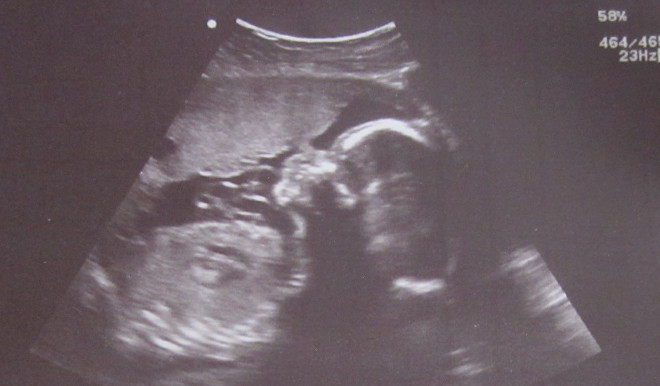

Here’s Baby’s latest picture. It’s a little hard to see, but Baby’s head is sideways and the left side is in shadow. You can see Baby’s chin (on the left), nose, and his/her right eye (near the top of the picture), which looks shut. Baby just might have been sleeping when this picture was taken. 🙂